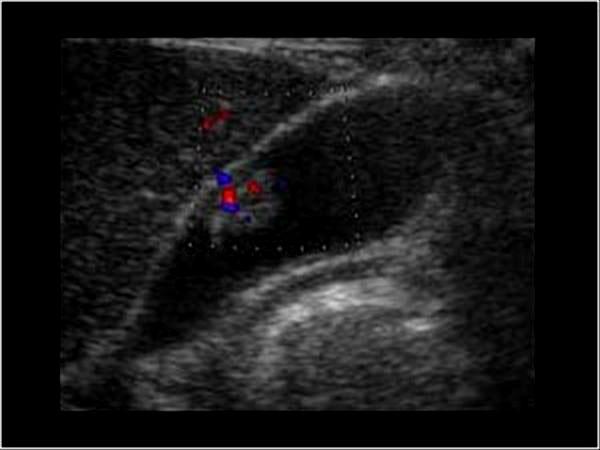

Portal Hypertension

Budd-Chiari

Life threatening emergency

Portal vein Thrombosis - cavernous transformation

replacement of the normal single channel portal vein with numerous tortuous venous channels.